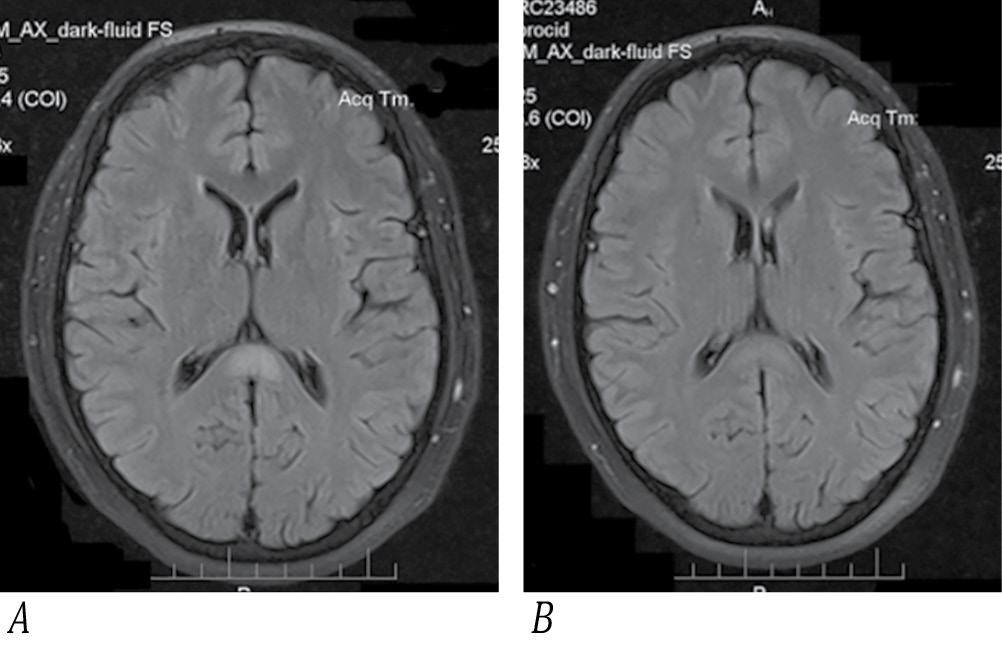

Рис. 2. МРТ пациента А. в режиме FLAIR, аксиальный срез головного мозга.

А — 1-й день госпитализации, в ВМТ — единичный симметричный очаг гиперинтенсивного МР-сигнала с достаточно ровными и чёткими контурами; В — 13-й день госпитализации, практически полный регресс очага.

Fig. 2. Axial brain FLAIR MRI of Patient A.

A: day 1 of hospitalization; a single symmetric hyperintense splenial lesion with relatively smooth and clear contours; B: day 13 of hospitalization; lesion almost completely resolved.